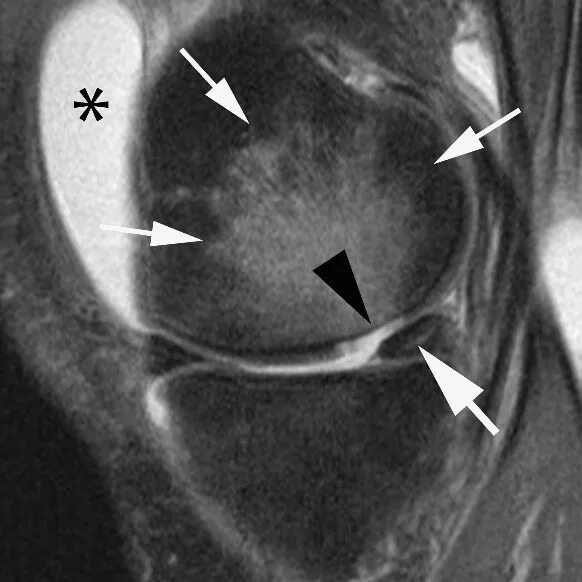

Мрт при боли в суставах